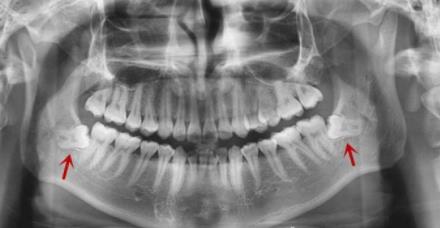

從(cong) 全景片中可以看出有兩(liang) 顆下頜智齒,這種智齒拔除後不用做假牙修複

比如說智齒,多生牙,以及滯留的乳牙,正畸需要拔除的牙齒等,這些牙齒拔除了就拔除了,反正本身也沒什麽(me) 作用,拔除了可以得到更好的結果,所以拔除後通常是不需要做其他處理的。而且也沒什麽(me) 大不了的,拔除後也就是不習(xi) 慣,會(hui) 用舌頭舔舔,習(xi) 慣了就好了。